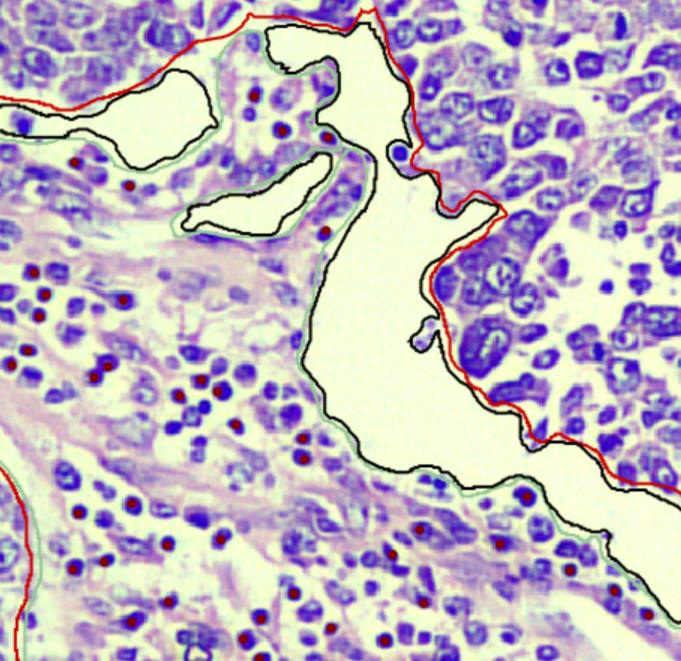

Grading & TME

Lesion grading (Gleason, Nottingham) and Tumor Microenvironment component annotation (TILs, Fibrosis).